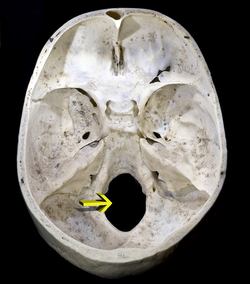

Foramen Magnum

The Foramen Magnum (Latin: great hole) is a large oval opening (foramen) in the occipital bone of the skull in humans and various other animals. It is one of the several oval or circular openings (foramina) in the base of the skull. The spinal cord, an extension of the Medulla Oblongata, passes through the foramen magnum as it exits the cranial cavity.

Apart from the transmission of the Medulla Oblongata and its membranes, the foramen magnum transmits the vertebral arteries, the anterior and posterior spinal arteries, the tectorial membranes and alar ligaments. It also transmits the spinal component of the accessory nerve into the skull.[1]